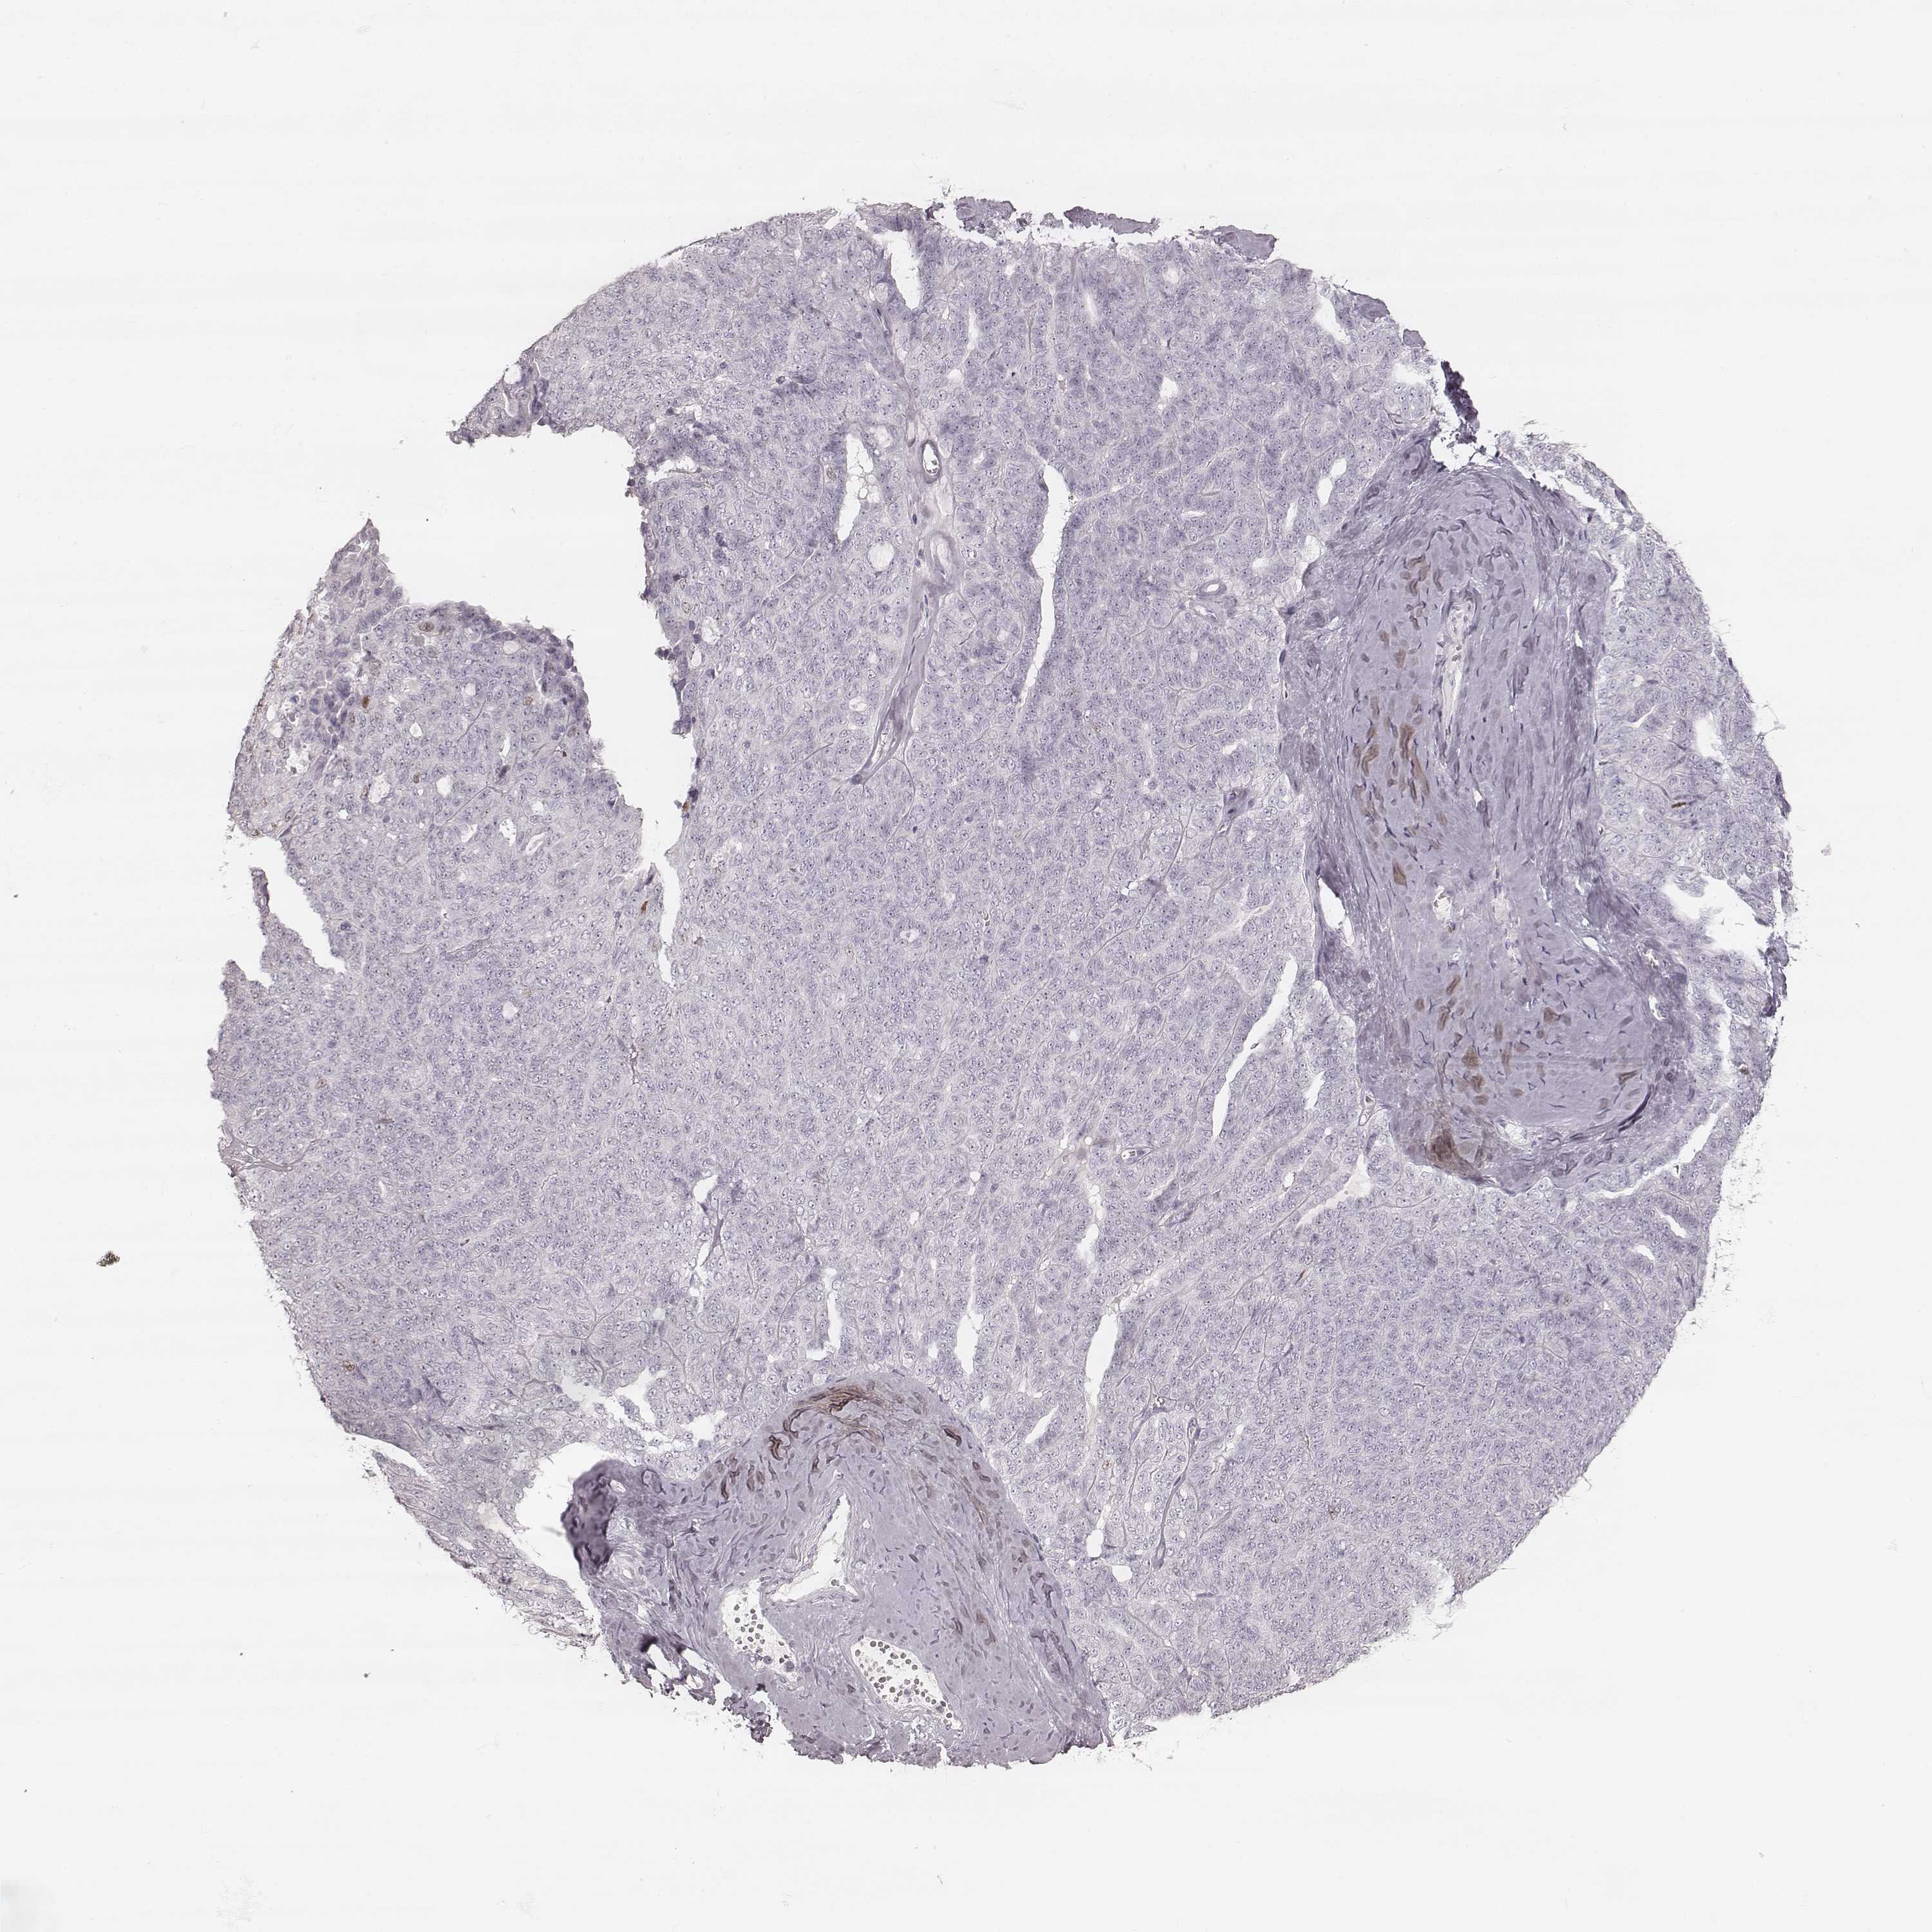

OVARIAN CANCER - Protein expressioni

A mouse-over function shows sample information and annotation data. Click on an image to view it in a full screen mode. Samples can be filtered based on level of antibody staining by selecting one or several of the following categories: high, medium, low and not detected. The assay and annotation is described here.

Note that samples used for immunohistochemistry by the Human Protein Atlas do not correspond to samples in the TCGA dataset.

Antibody stainingi

Antibody staining in the annotated cell types in the current human tissue is reported as not detected, low, medium, or high, based on conventional immunohistochemistry profiling in selected tissues. This score is based on the combination of the staining intensity and fraction of stained cells.

Each image is clickable and will lead to virtual microscopy that enables deeper exploration of all samples and also displays staining intensity scores, fraction scores and subcellular localization as well as patient and tissue information for each sample.

Antibody HPA043987

Cystadenocarcinoma, serous, NOS

Cystadenocarcinoma, mucinous, NOS

Carcinoma, endometroid